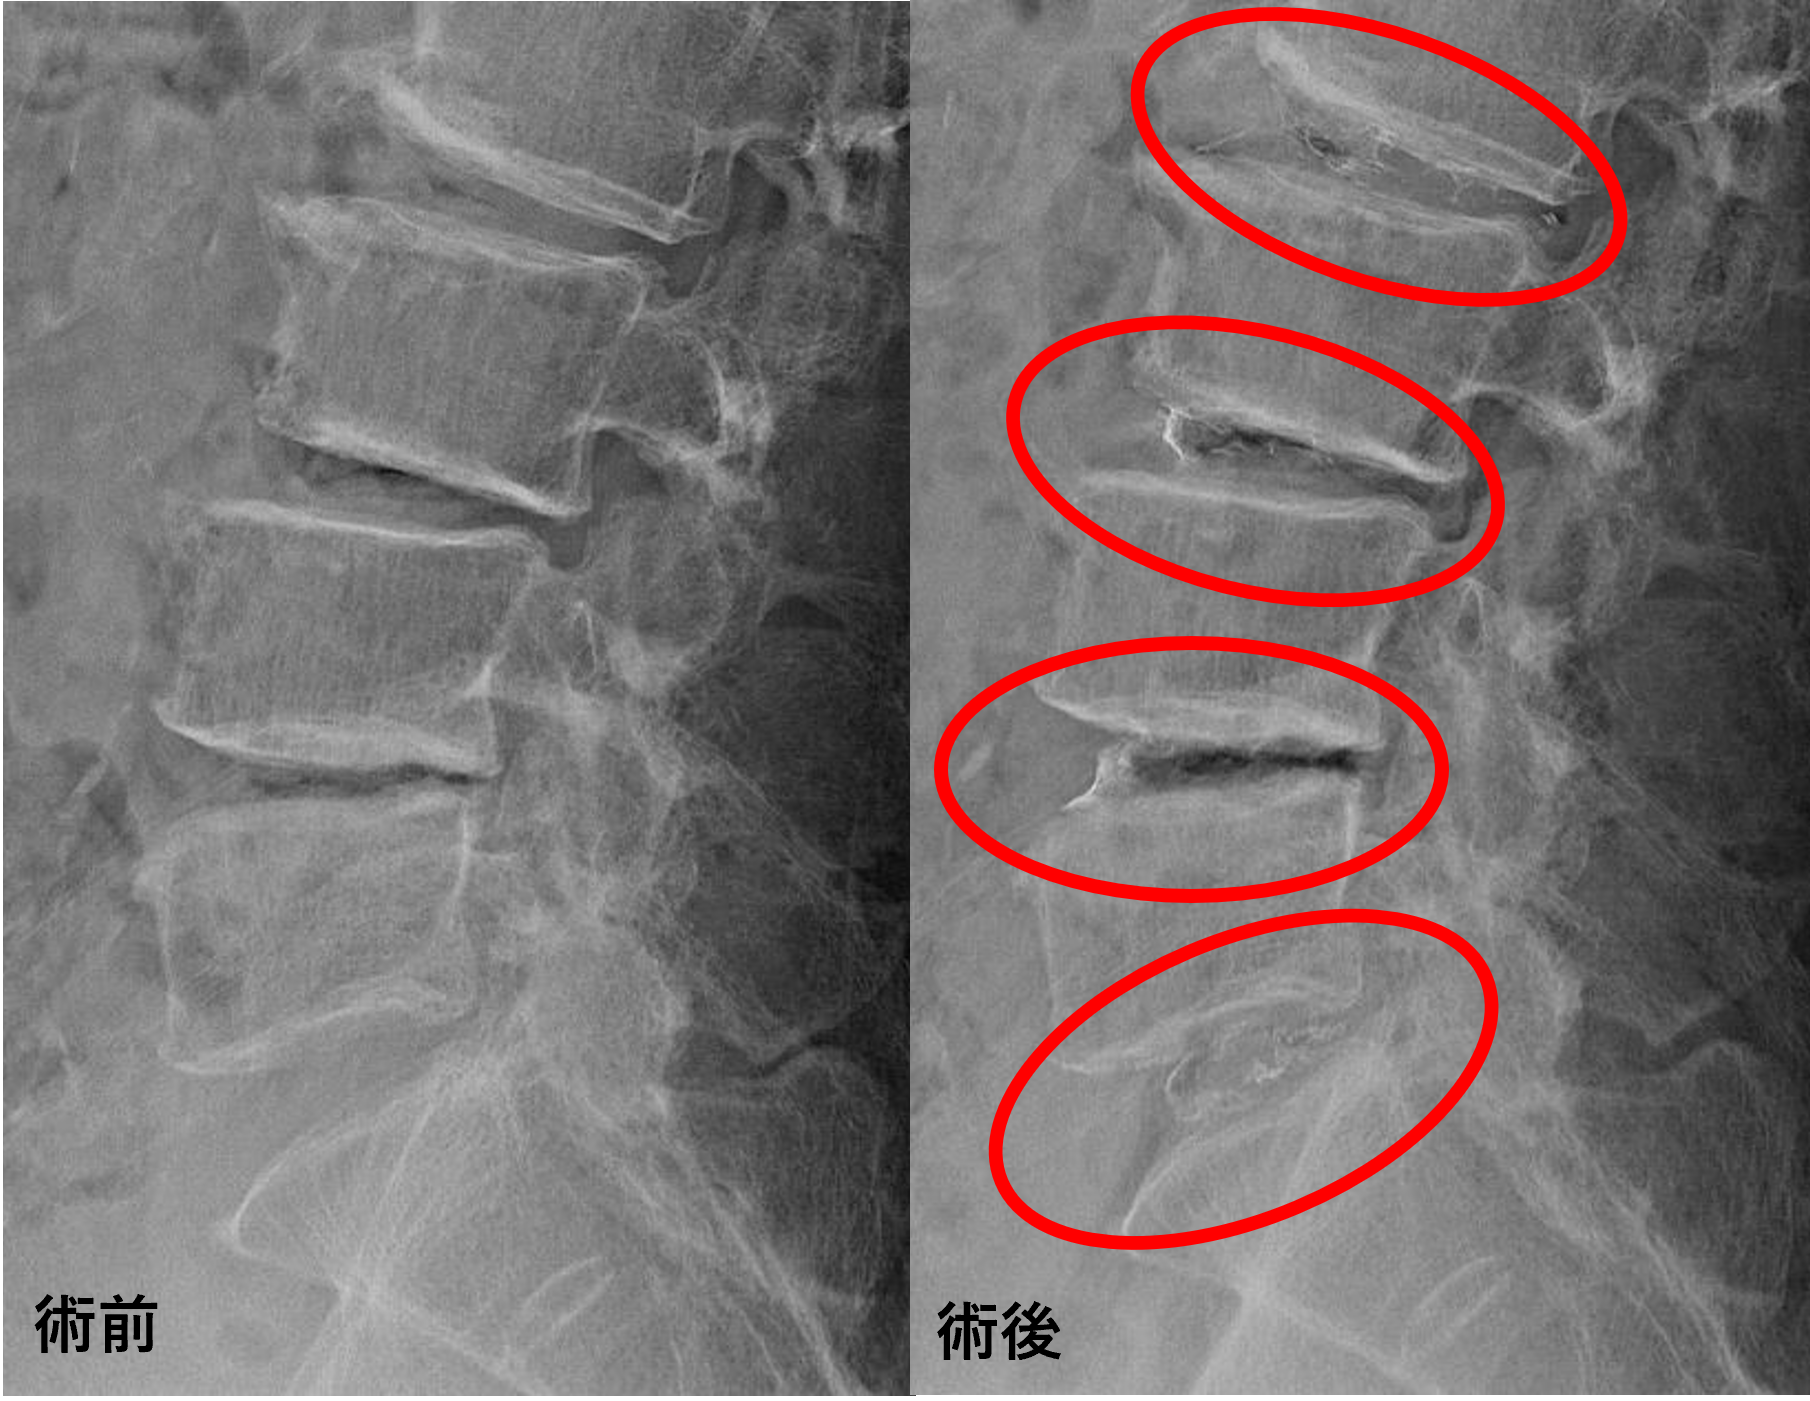

画像及び所見について

• L2/3、3/4、4/5 – 椎間板変性、膨隆、椎間孔狭窄、椎弓切除後

• L5/s – 椎間板変性、膨隆

以上のことが画像上認められました。

L2/3、3/4、4/5、5/sの椎間板所見による脊柱管の圧排が、症状の原因の可能性が高い。

患者様と相談の元、L2/3、3/4、4/5、5/sにセルゲル法を施行